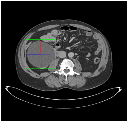

Self-paced curriculum learning (SCL) has demonstrated its great potential in computer vision, natural language processing, etc. During training, it implements easy-to-hard sampling based on online estimation of data difficulty. Most SCL methods commonly adopt a loss-based strategy of estimating data difficulty and deweighting the `hard' samples in the early training stage. While achieving success in a variety of applications, SCL stills confront two challenges in a medical image analysis task, such as universal lesion detection, featuring insufficient and highly class-imbalanced data: (i) the loss-based difficulty measurer is inaccurate; ii) the hard samples are under-utilized from a deweighting mechanism. To overcome these challenges, in this paper we propose a novel mixed-order self-paced curriculum learning (Mo-SCL) method. We integrate both uncertainty and loss to better estimate difficulty online and mix both hard and easy samples in the same mini-batch to appropriately alleviate the problem of under-utilization of hard samples. We provide a theoretical investigation of our method in the context of stochastic gradient descent optimization and extensive experiments based on the DeepLesion benchmark dataset for universal lesion detection (ULD). When applied to two state-of-the-art ULD methods, the proposed mixed-order SCL method can provide a free boost to lesion detection accuracy without extra special network designs.